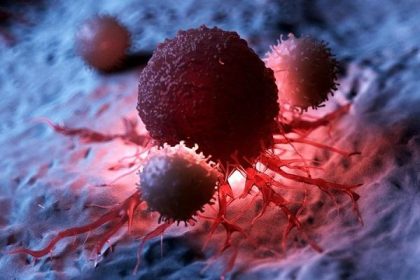

Oncologie : nécessité d’intensifier et d’adapter la formation spécialisée pour suivre le rythme des évolutions dans ce domaine

Les participants au colloque international sur l’oncologie, organisé vendredi à Sidi Bel-Abbès,…